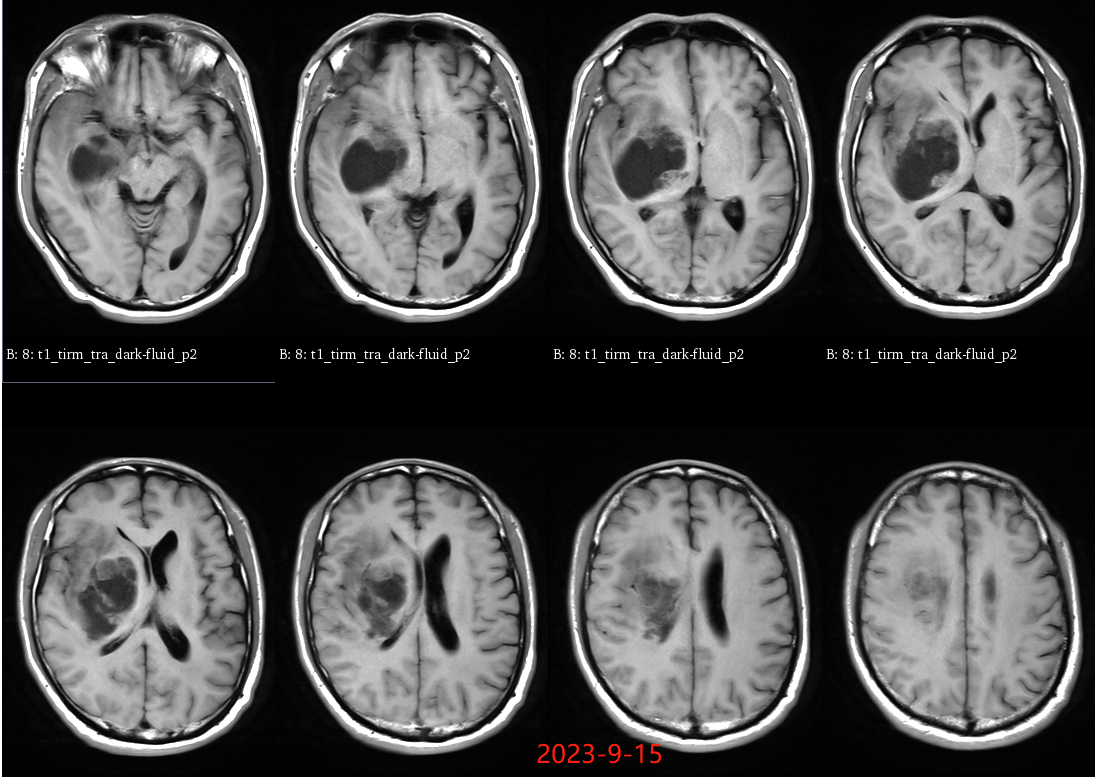

入院后于当地医院完善头颈部CTA检查未见明显血管发育异常,于2023-6-7行血肿钻孔引流术+脑室内颅内压监护探极置入术,引流一周后拔除引流管,期间未行尿激酶注射,患者反应情况逐渐好转,肌力未见明显改善。于出血后3周左右脑水肿基本消退后出院行康复治疗,治疗过程中患者肌力曾有所改善,左侧肢体肌力最好可达3级。术后3月左右患者一般状态逐渐变差,无发热,神志逐渐进展为昏睡状态,左侧肢体肌力1级,复查颅脑CT示水肿较前明显加重,颅脑MRI示右侧基底节区长T1长T2团块状病变,内有囊变,呈不均匀菜花样强化,考虑为高级别胶质瘤可能性大。遂行开颅病灶大部切除+去骨瓣减压术,术后病理提示高级别胶质瘤伴囊变,后续行同步放化疗STUPP方案,PTV:60Gy/30F/6周,替莫唑胺350mg化疗。患者右侧基底节区病灶相对稳定,2024-9-3复查颅脑MRI可见脑室内新发病灶。患者目前KPS 60分,神志清醒,精神差,反应迟钝,语言对答部分切题,右侧肢体自主活动,左侧肢体肌力2级。